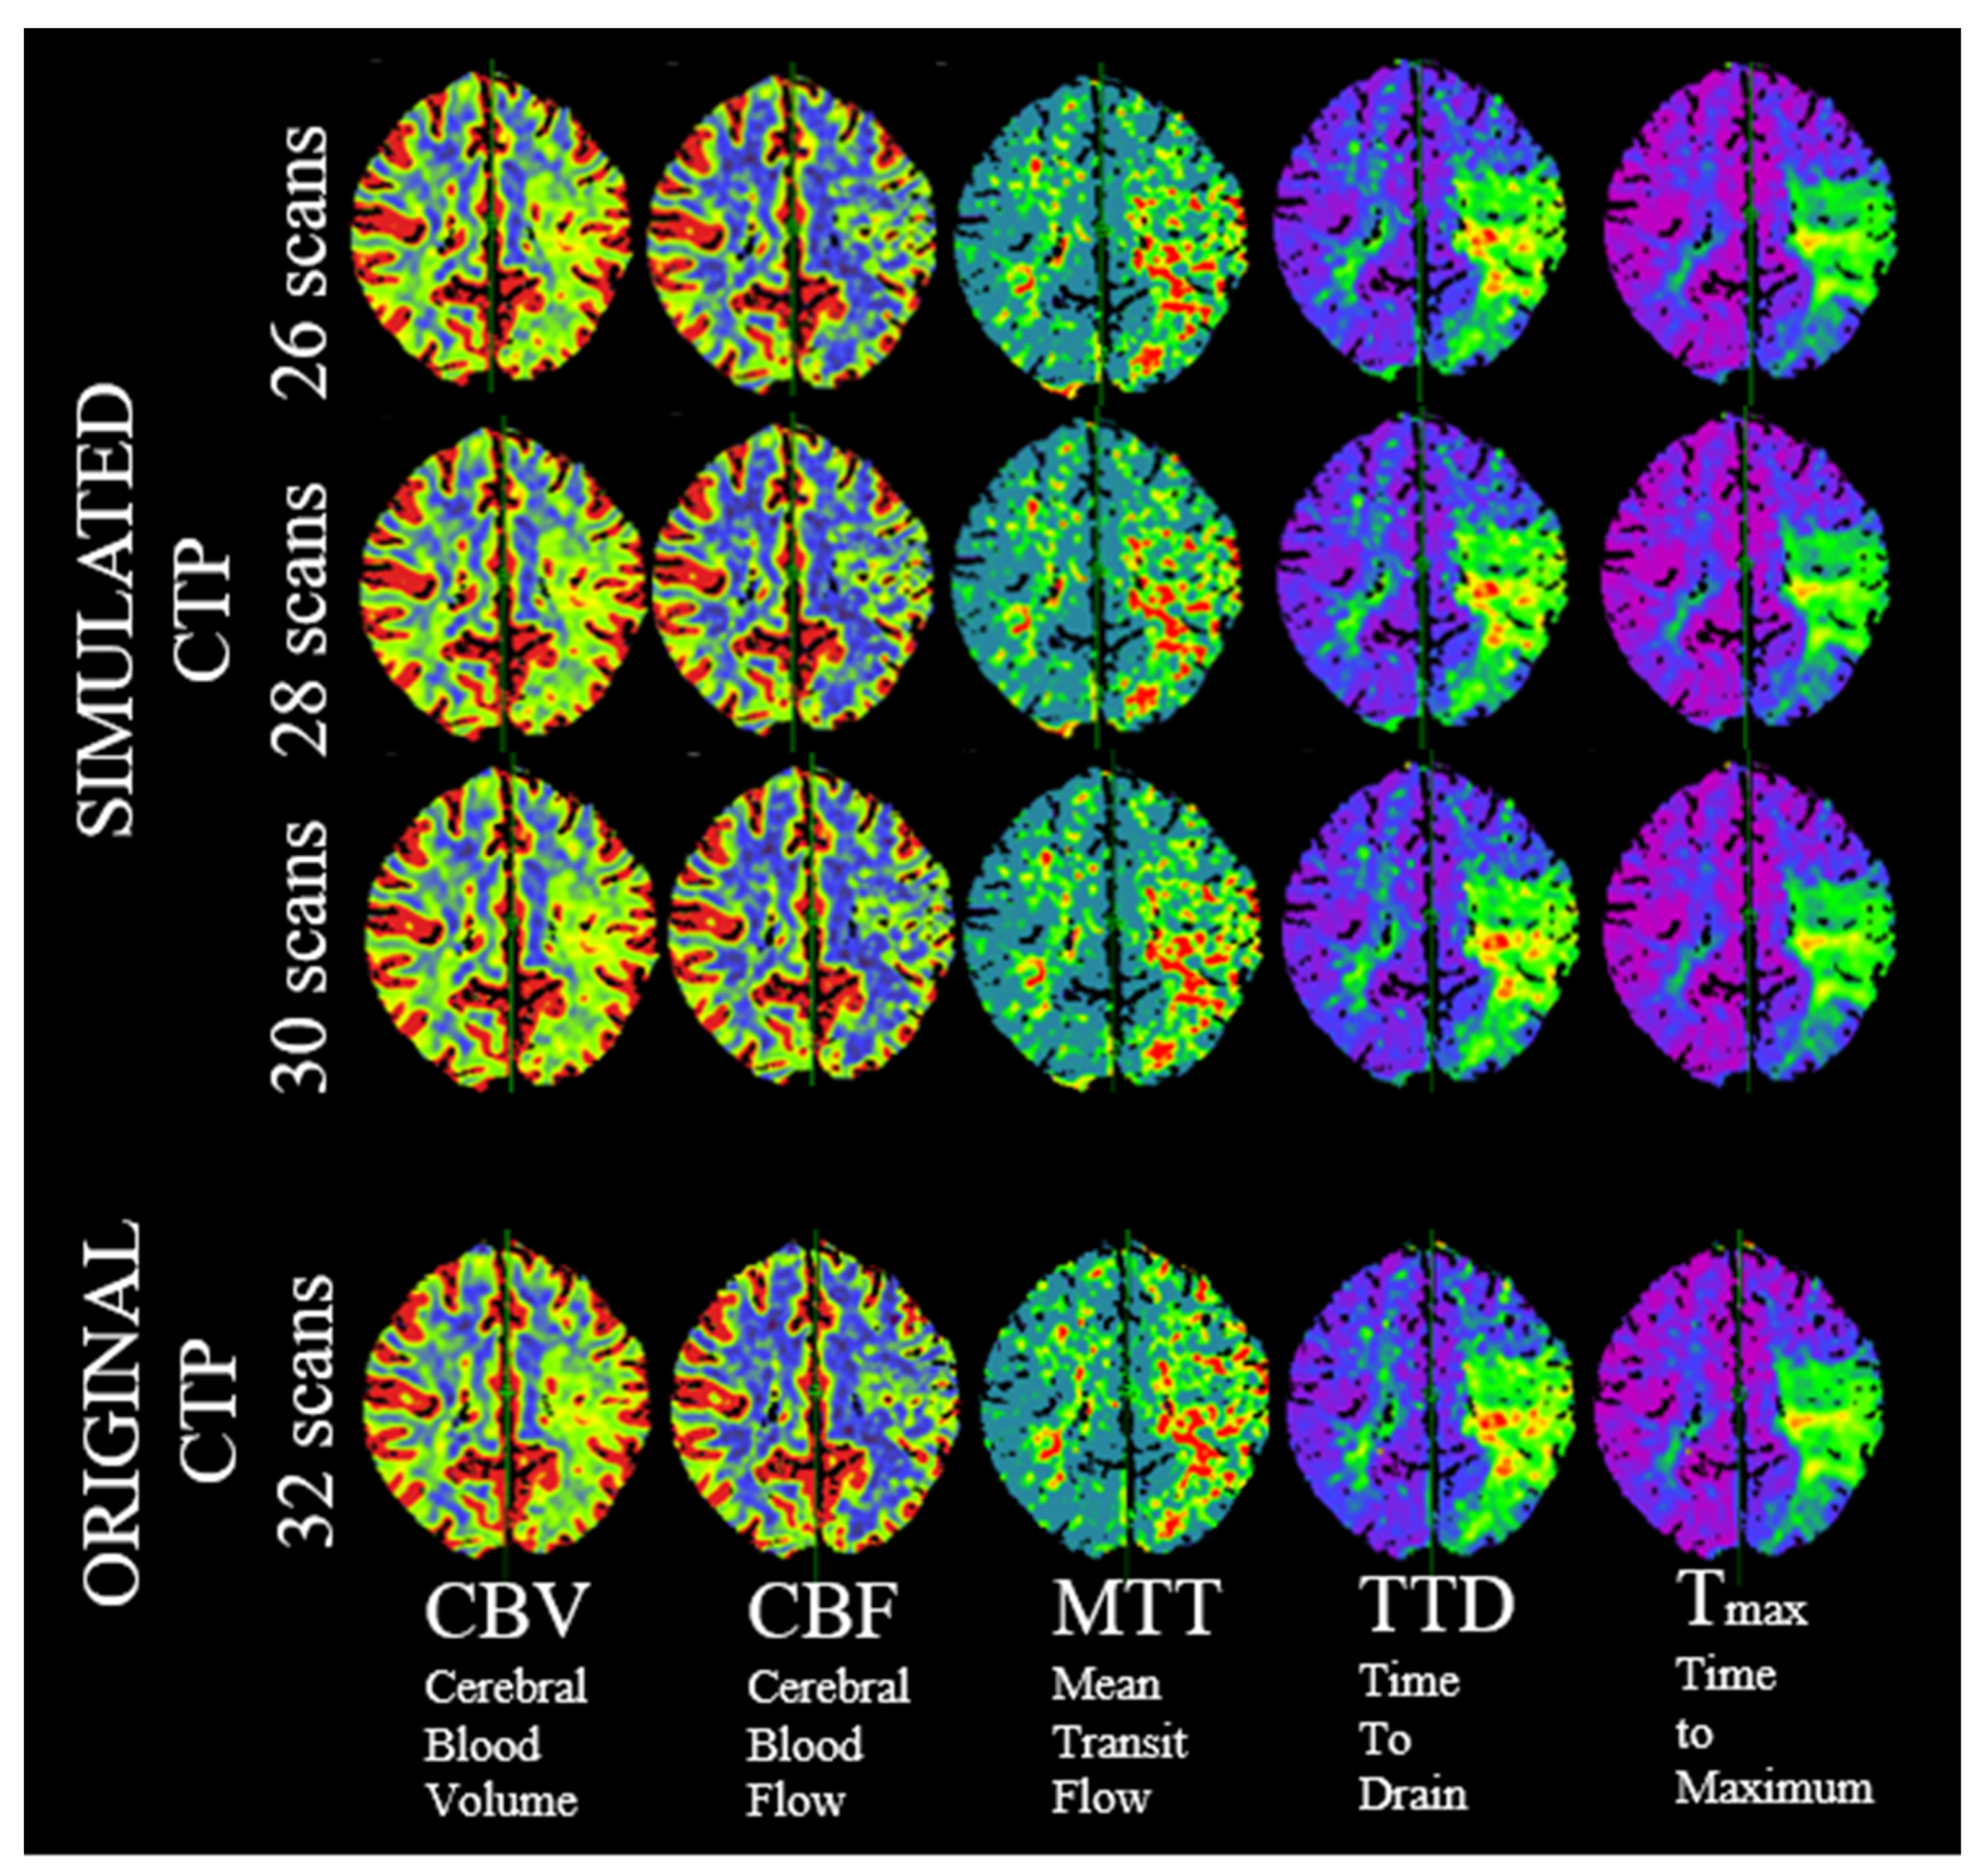

2.4. Study Design